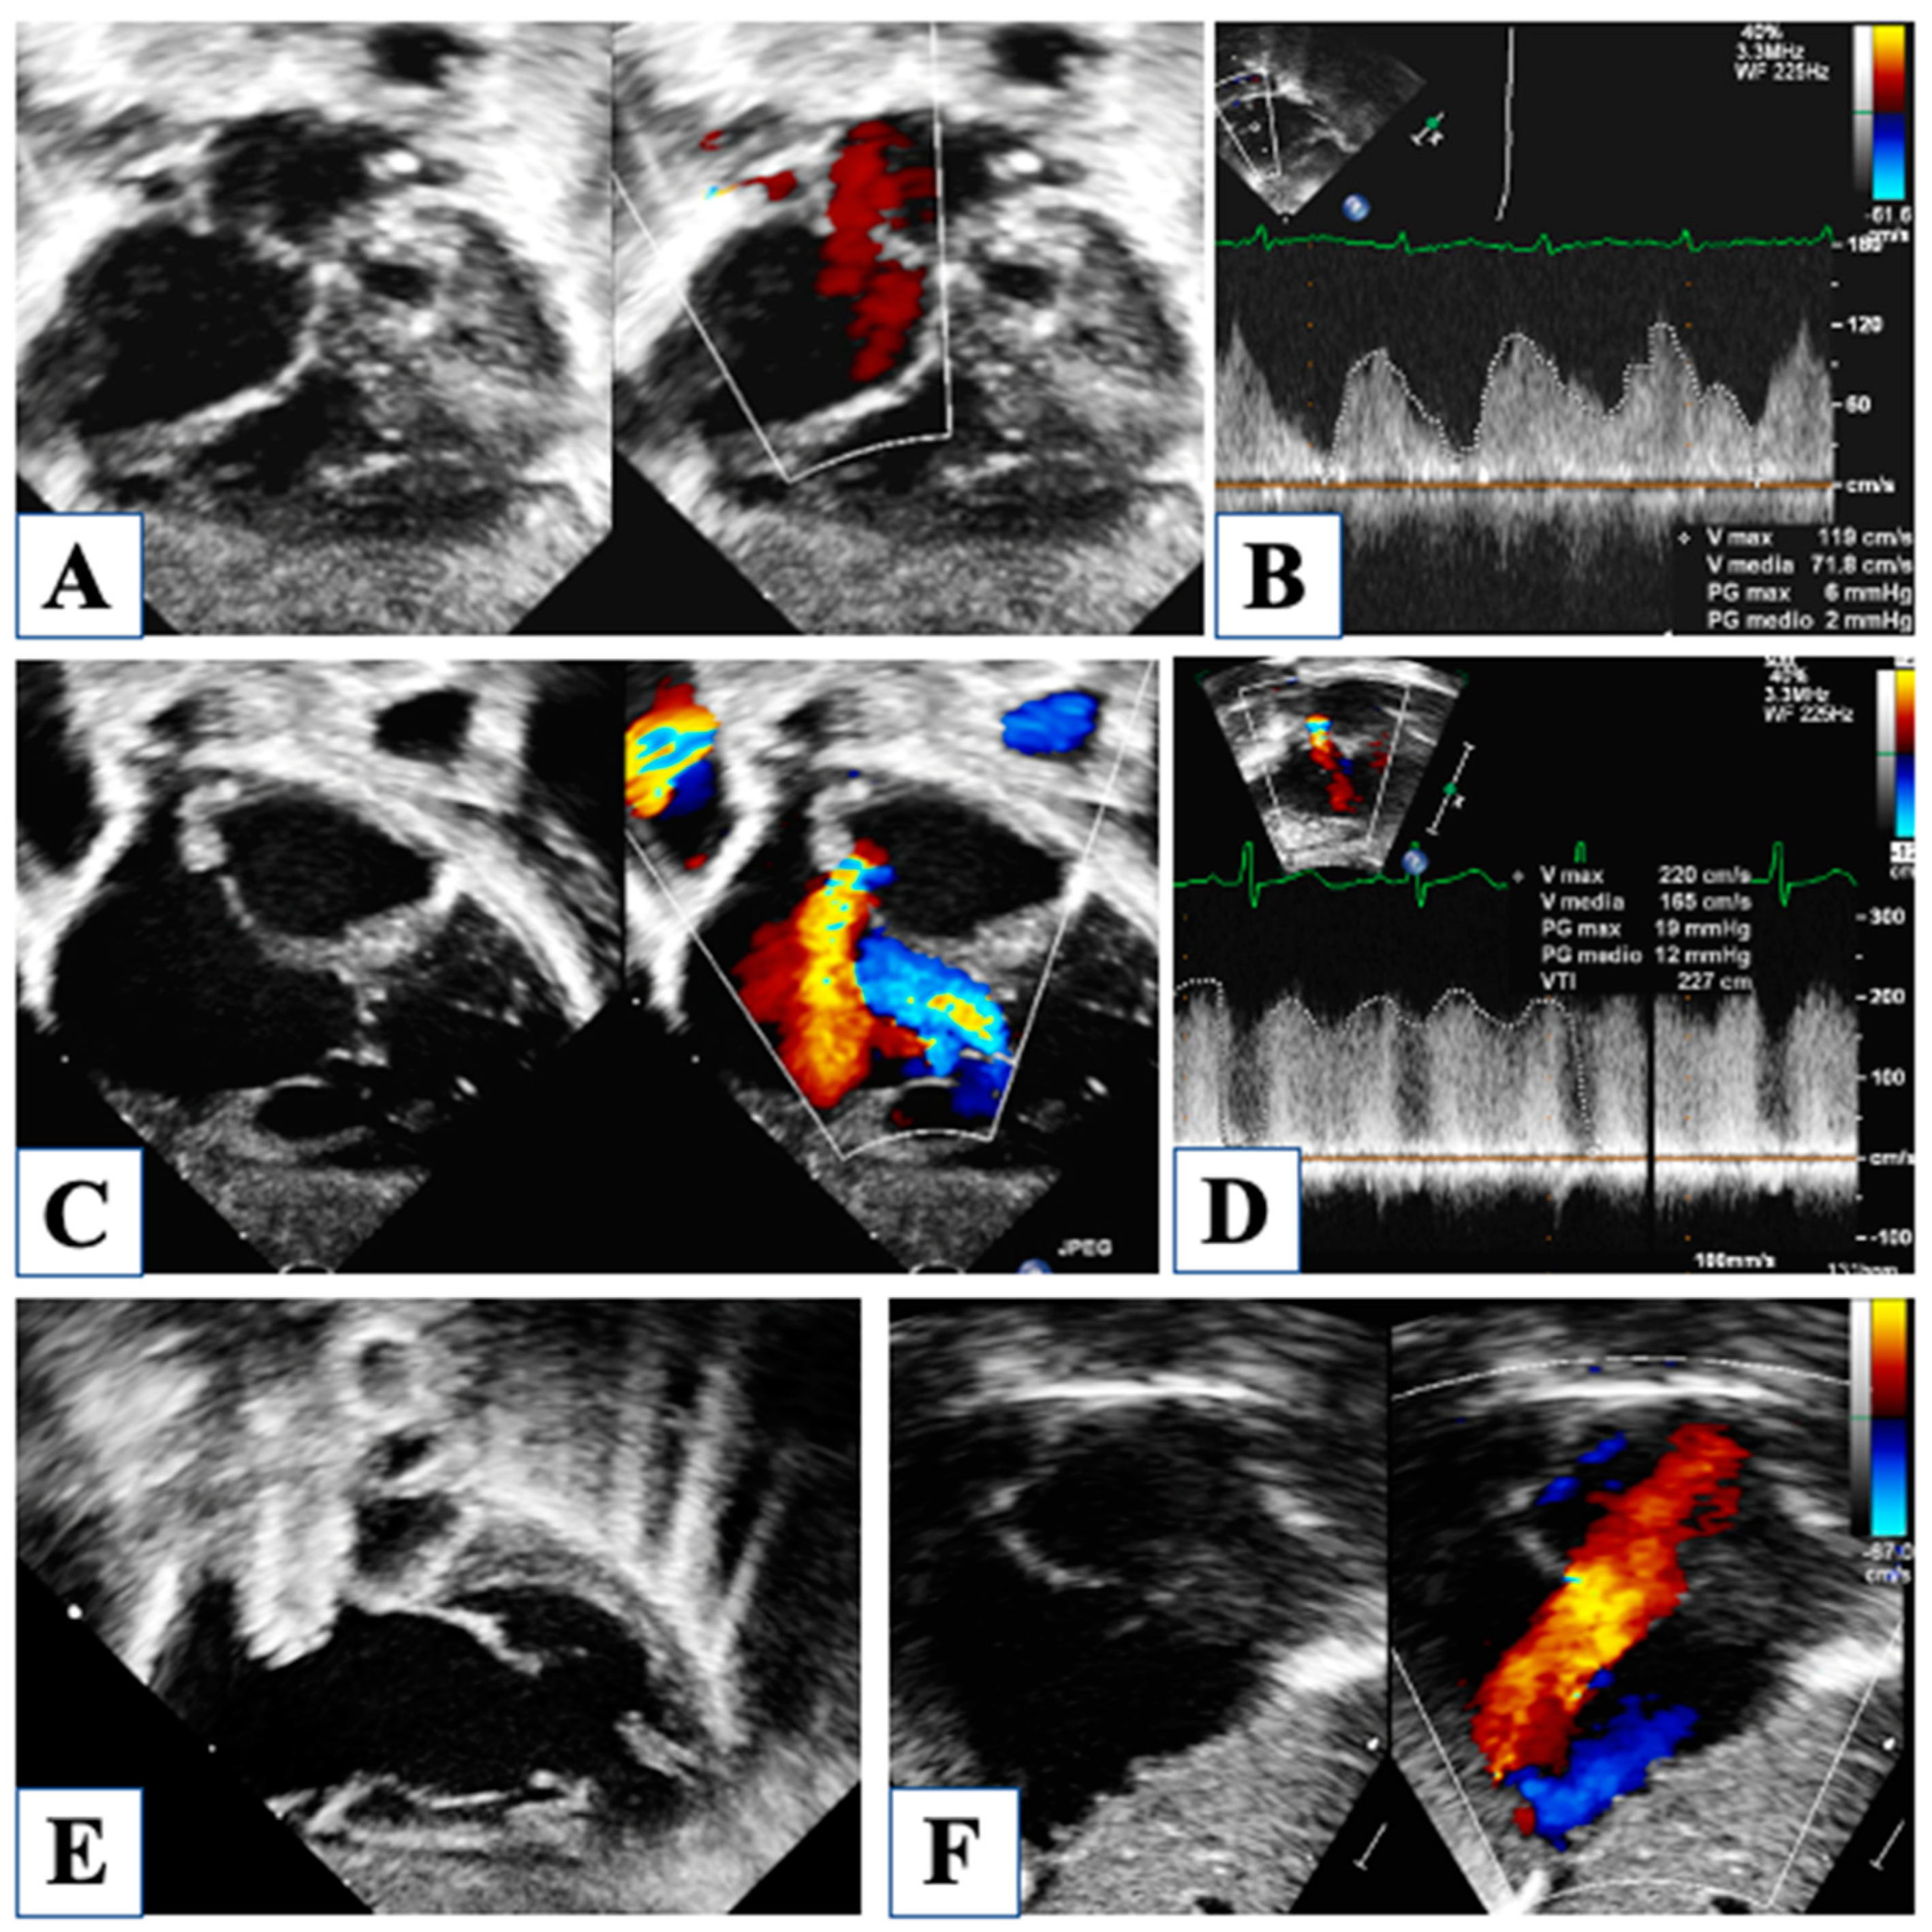

3. At Birth

4. Morphological Insights: The Borderline LV